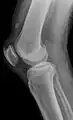

An x-ray demonstrating quadriceps tendon rupture. Note the abnormal angle of the patella and soft-tissue swelling marked by the arrow.